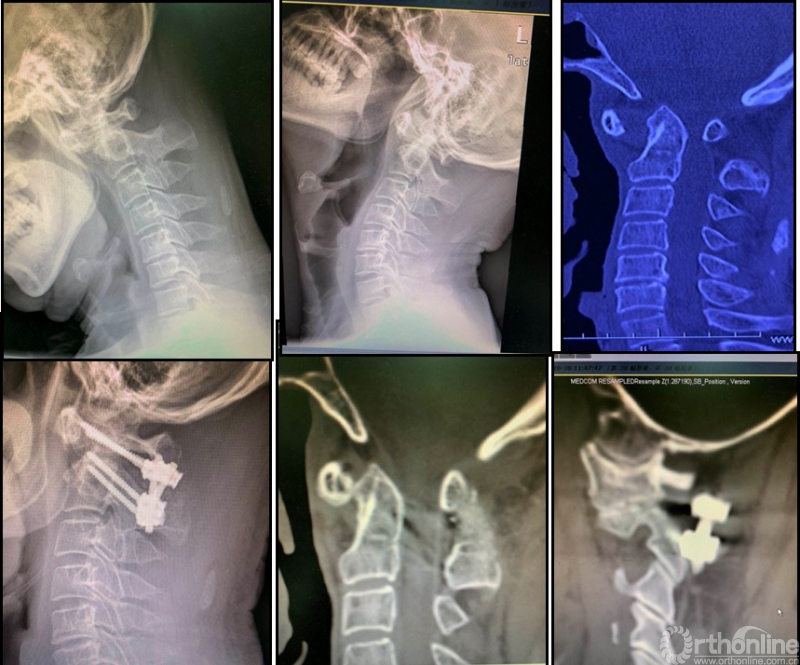

依据该诊治策略,我们可以为寰枢椎脱位患者制定周密的治疗策略(图3)。截至2020年,依托该策略进行诊治的病人已超过3000例。

图3:女性56岁;寰枢椎脱位合并寰椎枕骨化畸形、脊髓病。经过动力位X片及术中麻醉后牵引试验,诊断为“难复性寰枢椎脱位”(Type III)。行经口寰枢松解+后路C2椎弓根固定、枕颈固定融合术。寰枢椎脱位获得解剖复位、脊髓压迫解除。